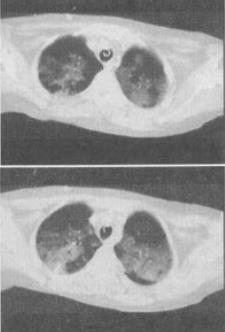

患者男,32岁,干咳,呼吸困难半月余,2个月前被诊断为艾滋病,结合影像学检查,最可能的诊断是()。

A、肺结核

B、卡氏肺囊虫性肺炎

C、肺癌

D、大叶性肺炎

E、间质性肺炎

正确答案:

B